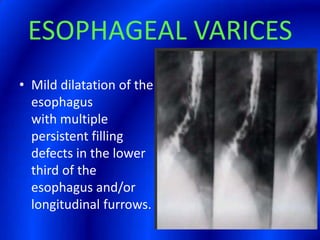

This document provides information about a barium swallow procedure. It begins with an introduction and overview of the embryology and anatomy of the pharynx and esophagus. It then describes the procedure itself, including preparation, technique, views obtained, and indications. Specific conditions that may be examined include pharyngeal and esophageal webs, foreign body impaction, scleroderma, dysphagia, mediastinal masses, and carcinoma. Diagrams are provided to illustrate normal anatomy and various pathological findings.